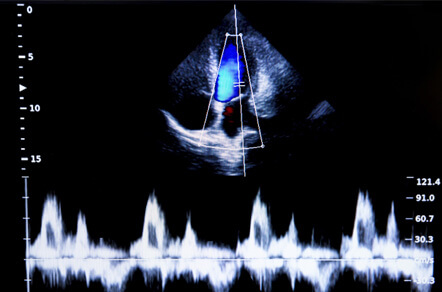

心臓超音波(エコー)検査

超音波(エコー)検査

エコー検査は、循環器内科・心臓内科の患者様にとって最も必要な検査の一つです。心筋梗塞や弁膜症、心不全などの状況を調べるだけでなく、生活習慣病である高血圧や糖尿病による心臓への影響をチェックする上でも欠かせない検査です。特に心臓の手術をした方は手術後の経過を診るためにも専門医による定期的なチェックをお勧めします。

当院では、循環器内科や心臓内科を牽引するクリニックとして、2019年のエコー検査を約2,300人のかたに行っております。

その中でも、当院で行った緊急エコー検査で重症の急性心不全や大動脈解離、心臓腫瘍など一刻を争う病気を発見された方も多くいらっしゃいます。

エコー検査はただ検査すれば良いというものではありません。信頼できる、そして経験豊富な施設での定期検査をくれぐれも欠かさないようにしましょう。